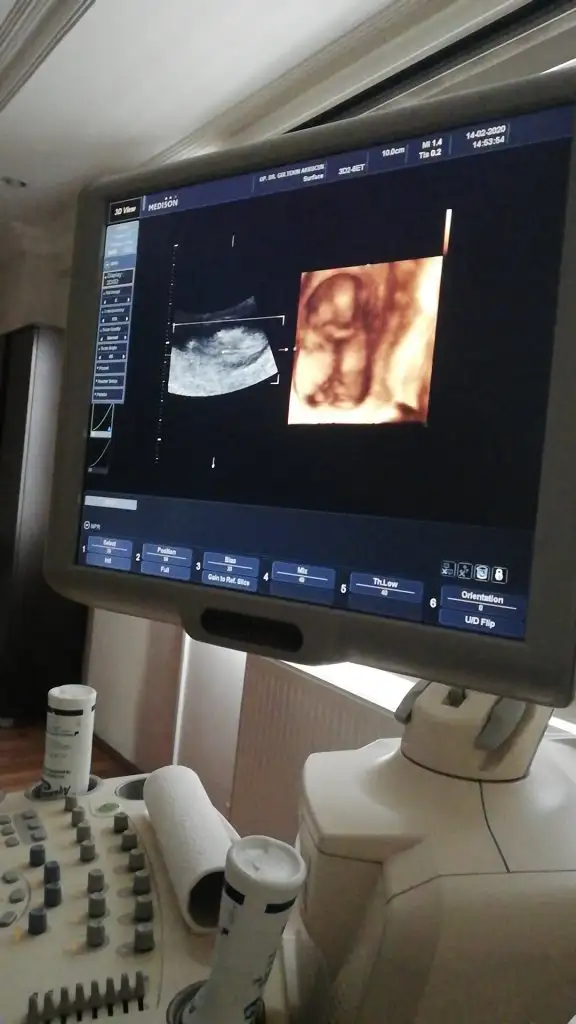

Bacak arası nubuda dik görünüyor erkek 11+2 dimi usg 12+ yada 13 olursa paylaşın A Aryaam

Canım 14+2 doktorum kıza benzetti dedim ben tereddutteyım daha önce erkeğe benzetildi ikili yltarama testinde İkra meyra

Dr. umda çok düşük ihtimal ile kız olabilir diye tahmin etti. Ama netlik için çok çok erken 2 hafta sonra netleşir dedi.

Canım ben 11+ yada 12 + nublara bakıyorum 14+2 de nub degil organı gelişmiş oluyor hadi 13 de olabilir usg dr kız dediyse kızdır cnm hmm 12 de erkek dedi diyorsun. hayırlısı olsun